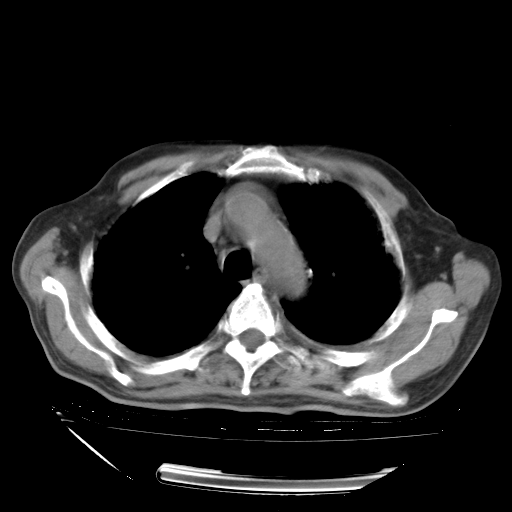

甲强龙80mg/日+抗结核治疗(异烟肼+利福霉素+乙胺丁醇)10天。复查肺部CT。

治疗10天肺部CT